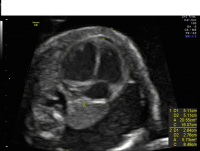

Hydrothorax coronal bilateral